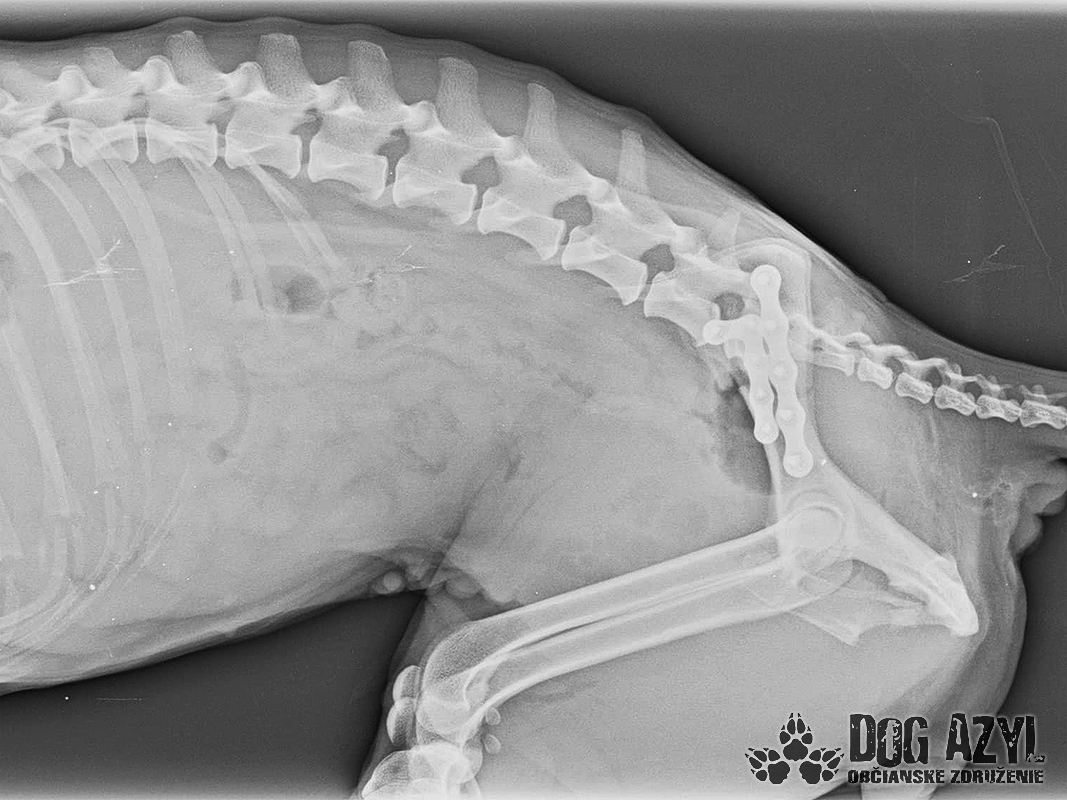

Mia, narodená máj 2015, sa našla zrazená v obci Bodza. Mala obrovské šťastie, že ju nálezkyňa ihneď naložila do auta a utekala s ňou k nášmu veterinárovi. Bola v katastrofálnom stave a mala obrovské bolesti :( Keďže Mia bola čipovaná, hneď sme sa dopátrali aj k majiteľom, ale na druhej strane telefónu nám bolo oznámené, že Miu darovali niekomu ale nemajú kontakt. Tak sme trocha pátrali a vypátrali sme, že Mia bola darovaná "do dobrých rúk" z postele priamo na dvor! Rodina sa tvárila veľmi zodpovedne a láskyplno, ale zrejme nepochopili,že Mia je kastrovaná a už nebude produkovať šteniatka. Po pár neúspešných pokus spáriť ju so samcom putovala do ďalších dobrých rúk" a to k miestnemu alkoholikovi, kde skončila v šope na reťazi a spala na kope hnoja :( Podarilo sa jej nejakým zázrakom ujsť, ale žiaľ skončila pod kolesami auta. Čomu sa vlastne ani nečudujeme, keďže cez tie zlepené chlpy nemala najmenšiu šancu vidieť pred seba. Mia podstúpila veľmi náročnú operáciu panvy, ktorá sa úspešne podarila, ale pri chladnejšom počasí zvykne trocha krívať. Mala tiež zlomený pst na zadnej nohe, ktorý sa zle zrástol a tak jej nechtík rastie trocha krivo a treba ho pravidelne strihať. Vôbec nič jej to však neuberá na kráse a chuti do života :) Mia si hľadá rodinu, ktorá jej vie sľúbiť, že ju nikdy viac neopustí. Je to skôr pokojná fenka, nie je vôbec náročná na pohyb ale na maznanie o to viac :) Veľmi rada sa túli k človeku, je veľmi priateľská a kontaktná. Vôbec jej nevadí spoločnosť iných psíkov ani mačiek ale nepotrebuje ich ku svojej spokojnosti :) Mia je dokonale vhodná do bytu, ale k malým deťom určite nie, má totiž rada svoje súkromie. Ak by sa mala adoptovať k rodinnému domu tak podmienkou je bývanie v dome.